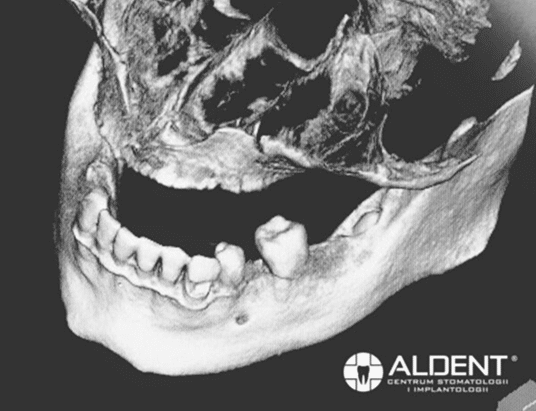

Implanty zygomatyczne są rewolucyjnym rozwiązaniem dla pacjentów z rozległymi zanikami kostnymi szczęki. Ten rodzaj implantów dedykowany jest bezzębnym pacjentom, u których jeszcze kilka lat temu było niemożliwe uzupełnienie braków zębowych tradycyjnymi implantami. Implanty zygomatyczne opracował szwedzki profesor Per-Ingvar Branemark. Ów twórca leczenia implantologicznego odkrył, że kość jarzmowa ma odpowiednią strukturę i objętość pozwalającą na osteointegrację implantów, dzięki temu dał szansę wielu pacjentom na komfortową odbudowę utraconych zębów. Implanty zygomatyczne wprowadzane są w odcinkach bocznych w okolicę kości jarzmowej, dlatego nazywane są też implantami jarzmowymi. Charakteryzują się tym, że są znacznie dłuższe od tradycyjnych implantów. Ich długość wynosi od 30 do ponad 50 mm. Wykonane są w całości z tytanu czyli materiału kompatybilnego i biozgodnego z organizmem człowieka.

Implanty zygomatyczne wprowadzane są pod kątem 45 stopni do kości jarzmowej. Dzięki wielopunktowemu zakotwiczeniu kortykalnemu oraz gwintowanej konstrukcji wierzchołka, zapewniają one odpowiednią stabilność uzupełnienia protetycznego. Wykonane z tytanu, są biokompatybilne i bezpieczne dla organizmu pacjenta.

Za pomocą czterech implantów zygomatycznych możemy odbudować cały łuk zębowy

Podczas pierwszej wizyty przeprowadzamy szczegółowy wywiad medyczny oraz badanie kliniczne jamy ustnej. Niezbędnym elementem diagnostyki jest wykonanie tomografii komputerowej 3D (CBCT), która pozwala na precyzyjne ocenienie warunków kostnych pacjenta i szczegółowe zaplanowanie zabiegu. Po kwalifikacji pacjenta do zabiegu, ustalamy termin zabiegu i przekazujemy zalecenia przedzabiegowe.

Przed zakwalifikowaniem pacjenta do zabiegu implantologicznego, w klinice CSK Aldent przeprowadzamy szczegółowy wywiad medyczny oraz dokładne badanie kliniczne jamy ustnej. Naszym priorytetem jest bezpieczeństwo i komfort pacjenta, dlatego każda konsultacja rozpoczyna się od precyzyjnej diagnostyki z wykorzystaniem stożkowej tomografii komputerowej (CBCT). Ta zaawansowana metoda obrazowania pozwala naszym implantologom na maksymalne wykorzystanie podłoża kostnego pacjenta oraz na precyzyjne zaplanowanie każdego zabiegu.